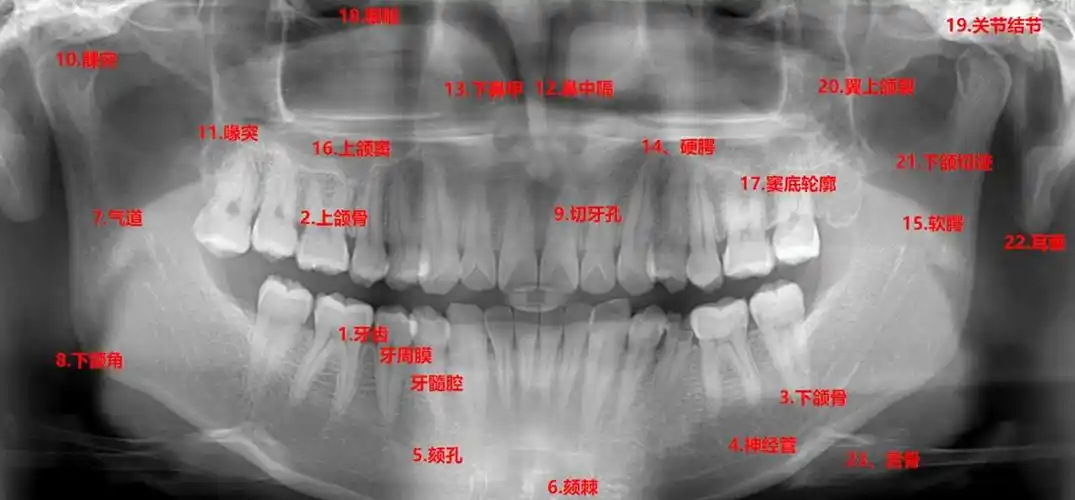

口腔全景片(曲面断层片)是口腔科检查中十分重要的常规检查手段,主要

伯爵cbct影像篇③口腔全景片认知

怎么看口腔全景片